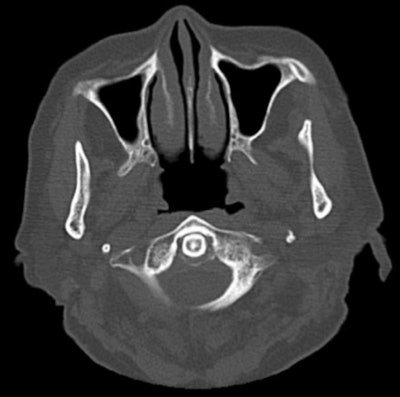

Plain CT scan showing calcification surrounding the odontoid process. An axial CT scan of the cervical spine shows calcification on the posterior aspect of the odontoid process.

A cervical x-ray showed no abnormalities. However, a cervical computed tomography scan revealed calcification surrounding the odontoid process, which was consistent with crowned dens syndrome, they wrote.